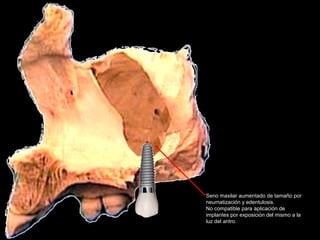

Tomografía computarizada

De seno maxilar corte sagital.

Area de implantación

Dentaria.

Material osteoconductor

para elevar el piso antral

Nuevo piso del seno y su

margen de seguridad para

contener el implante

dentario

Antro maxilar visto desde la cara interna del un hueso

Aparentemente normal

Seno maxilar aumentado de tamaño por

neumatización y edentulosis.

No compatible para aplicación de

implantes por exposición del mismo a la

luz del antro.

Colocación de material biológico o

no para aumentar el espesor del

piso y poder contener implante

dentario en un lecho de “hueso

sano”.

Uno de los fenómenos fisiológicos más comunes es la falta de hueso en el

Piso del antro de Highmore, secundario a la neumatización de los senos y

Que en muchas ocasiones aproxima el piso antral al proceso alveolar, por

Lo que sobre todo en pacientes jóvenes es factible dar volumen a este

Área con la aplicación de injerto de hueso humano, equino o derivados de

arcillas de sílice. Las indicaciones de usar uno u otros depende de la experiencia

Clínica del operador.